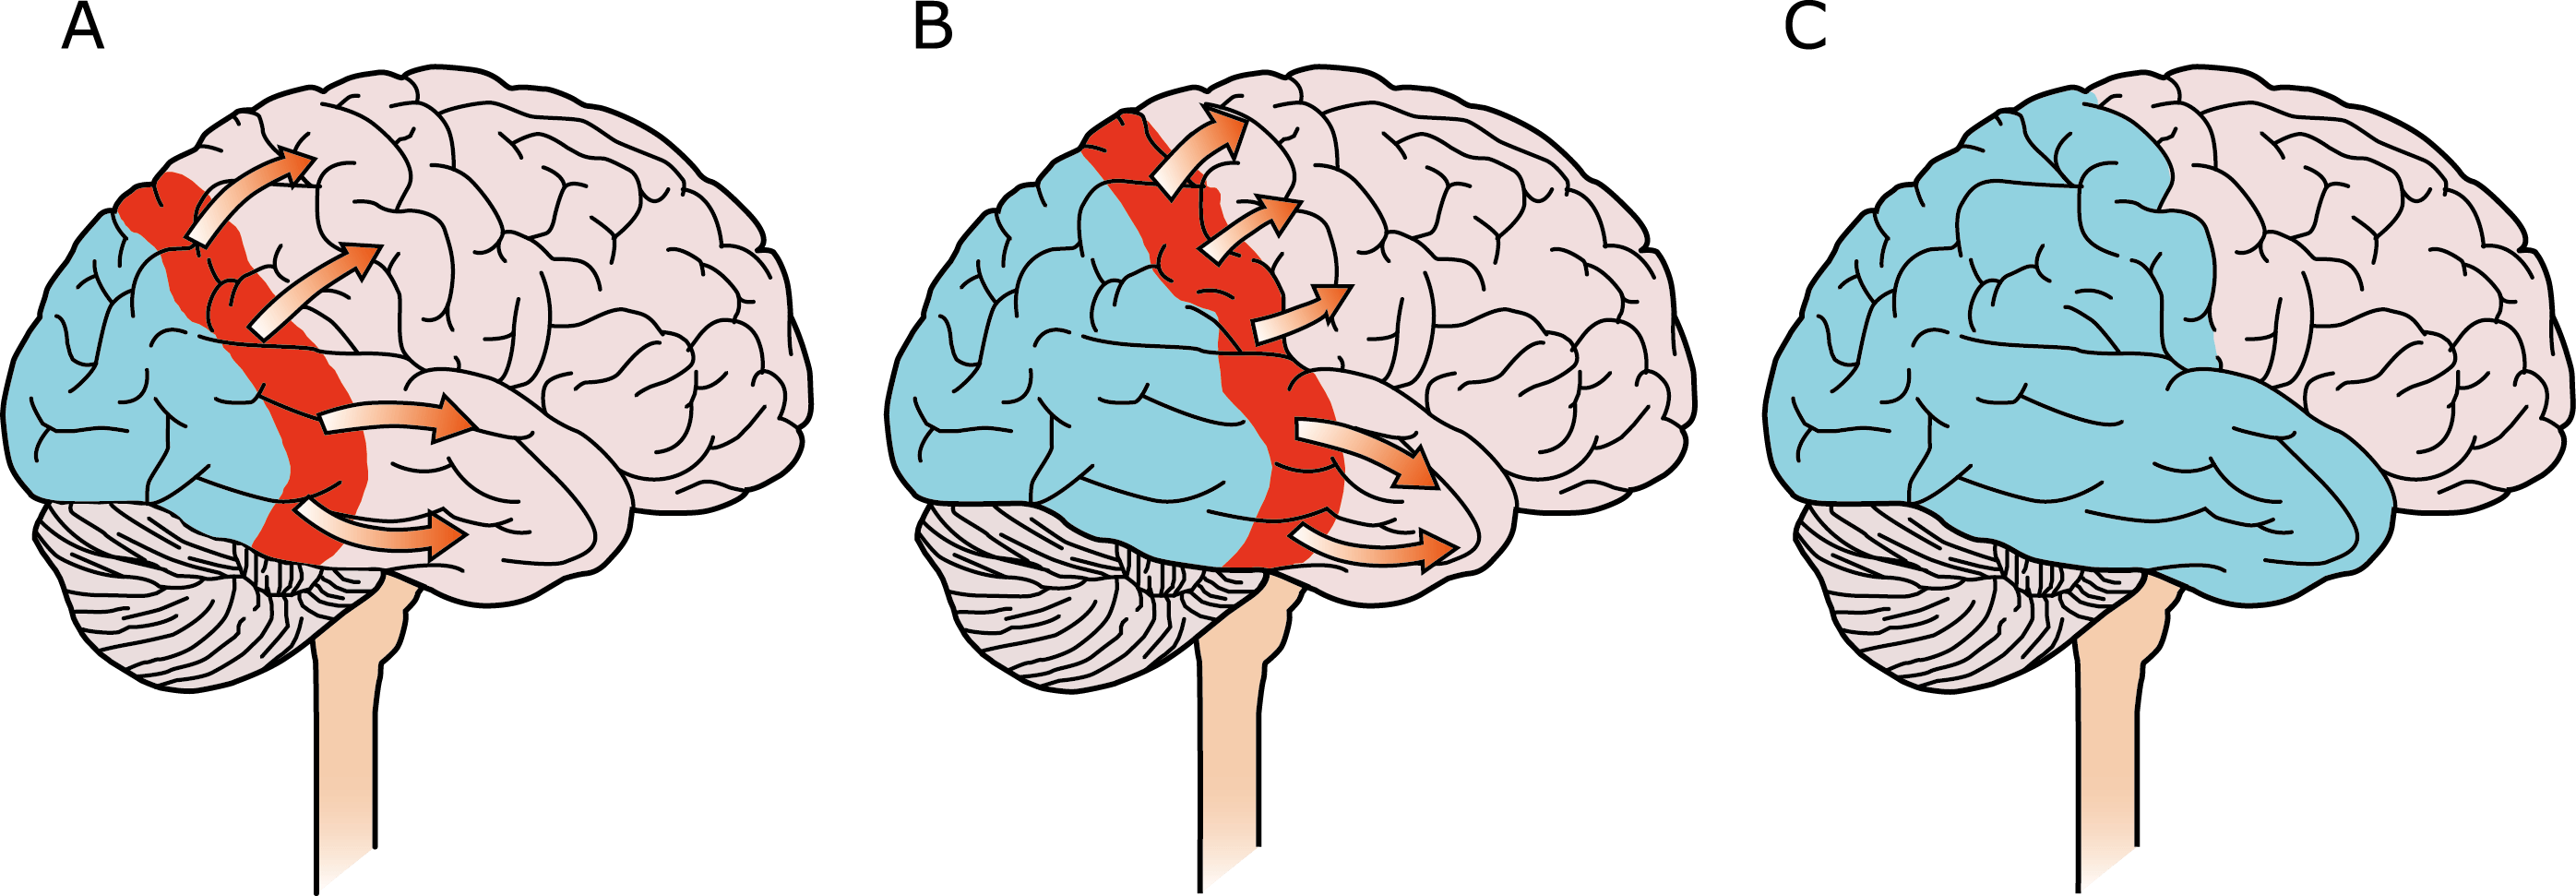

El aura de la migraña, al menos en su sentido clásico, tiene relación con la depresión cortical que se propaga por la corteza cerebral y participa como un actor paralelo cuando se producen las crisis. (Figura 2)

Se cree que una onda transitoria de despolarización neuronal de la corteza (Figura 9), la depresión de propagación cortical (CSD), es el mecanismo cerebral fisiopatológico subyacente al fenómeno clínico del aura de la migraña. Leão(21) estableció un mecanismo subyacente hipotético. Luego de haber estimulado eléctricamente la corteza de conejo y encontrar una depresión EEG que se propagaba a una velocidad similar de 3 mm/min centrífugamente desde el sitio de estimulación sugirió que podría ser la base del aura migrañosa. Esta hipótesis está fundamentada en la correlación entre las características neurofisiológicas de una CSD, su propagación retinotópica en la corteza visual y las características y dinámicas de los déficits visuales(14, 15) y en las observaciones indirectas derivadas de los estudios de imágenes que respaldan aún más este concepto(16) Sin embargo, sobre la base de la comprensión actual de la migraña, es poco probable que la CSD esté involucrada en el inicio del síndrome completo de la migraña(17).